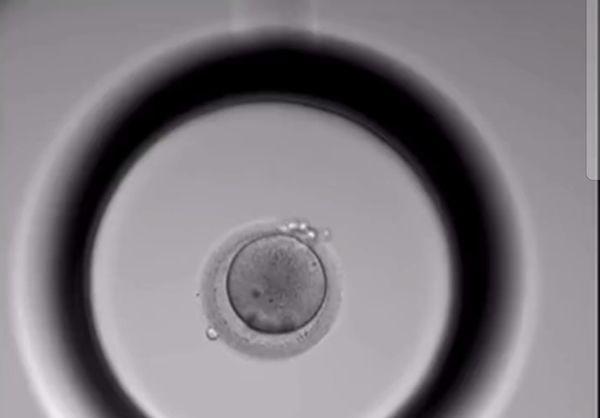

胚胎培养第1天半:精卵结合后形成了受精卵,清晰可见两个细胞核